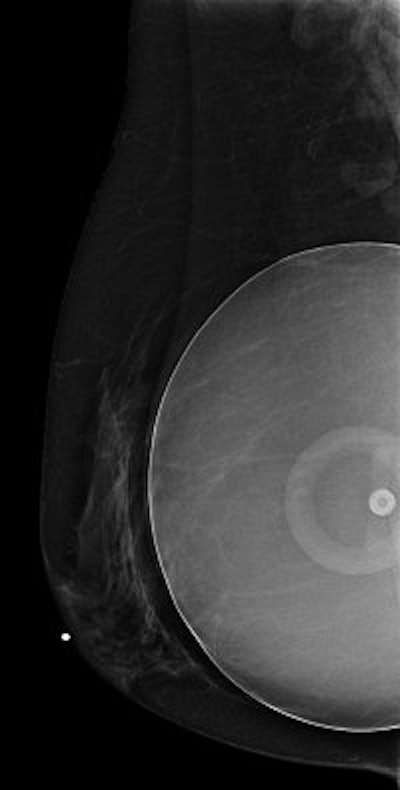

MRI

Mammography is still the best tool for breast cancer screening, and there are currently no recommendations for using MRI as a cancer screening tool in women with implants, but it can be helpful in selected cases. It's an excellent tool for imaging the augmented breast, including the implant itself and the breast tissue surrounding it.

![]() |

| Representative MR image of 220-mL single-lumen silicone gel-filled implant placed December 20, 1982, shows presence of multiple-layered wavy lines representing collapsed implant shell surrounded by silicone gel (i.e., linguine or wavy-line appearance). Brown SL, Middleton MS, Berg WA, Soo MS, Pennello G, "Prevalence of Rupture of Silicone Gel Breast Implants Revealed on MR Imaging in a Population of Women in Birmingham, Alabama" (American Journal of Roentgenology, 2000;175:1057-1064). |

Analog mammography cannot penetrate silicone or saline implants well enough to image the overlying or underlying breast tissue. Implants can obscure some of the breast tissue on mammography, making abnormalities or signs of breast cancer more difficult to see. MRI imaging does not have these limitations. It's also well-suited for demonstrating implant leakage or rupture, and for imaging breast tissue that is compressed by the implant. There are some patient limitations, such as claustrophobia or the inability to lie facedown on the exam table.